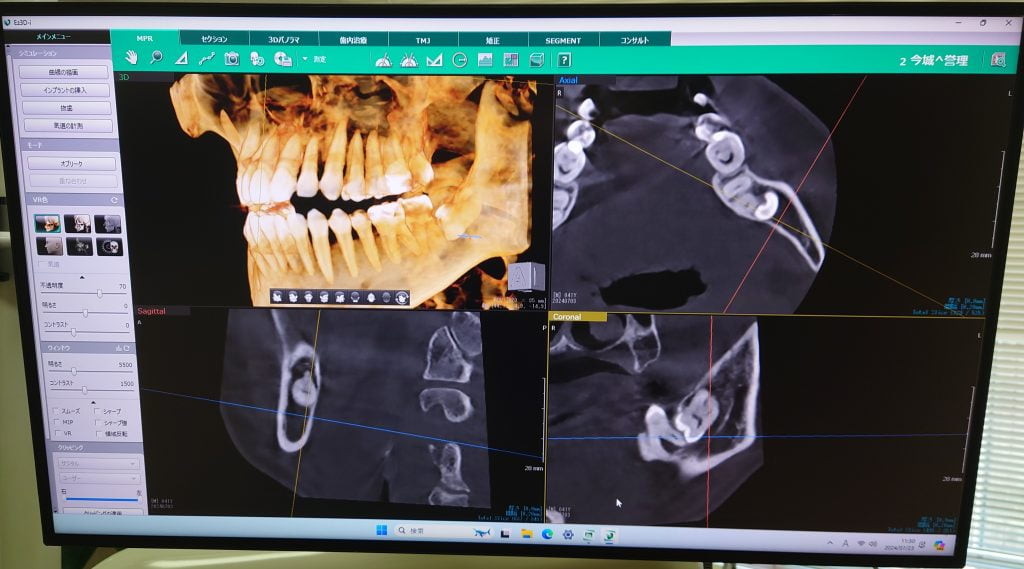

CTとは撮影装置とコンピューター処理により撮影データを3次元的に構築し、骨の状態などが正確、高精度に診断できる装置です。レントゲンでは判別が難しい骨の厚みや密度も簡単に計測できるようになり、診断がより正確にできます。レントゲンもCTも同じものではありますが、レントゲンは2次元の平面での診断ができませんが、CTでは3次元の立体画像の情報を得られます。

虫歯が大きくて神経をとる治療においては今までのレントゲンでは細かい神経の穴の場所を把握できませんでしたが、CTにより場所を正確に立体化できるため細かい神経の穴の場所を認識しやすくなりました。

インプラント治療において

インプラント治療の成功率が上がる骨の量、骨密度がCTにより正確に把握することができます。

インプラントは骨の中にネジを埋入するものですが、深さ・幅・角度を正確にシミュレーションすることができます。ですので治療の際安全性が格段に向上します。